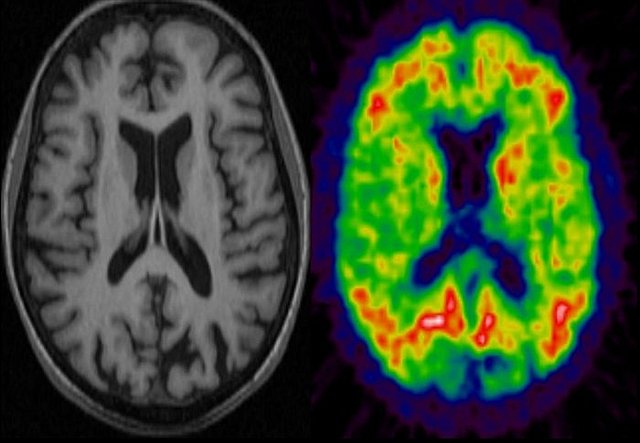

Nuevas tecnologías

Durante esta década se fortalece la investigación con el empleo de imágenes no ya anatómicas sino funcionales, en particular la resonancia magnética funcional (MRI, por sus siglas en inglés, imagen de la izquierda) y la tomografía por emisión de positrones (PET, imagen de la derecha), que han permitido visualizar la actividad cerebral durante la realización de diferentes tareas cognoscitivas.